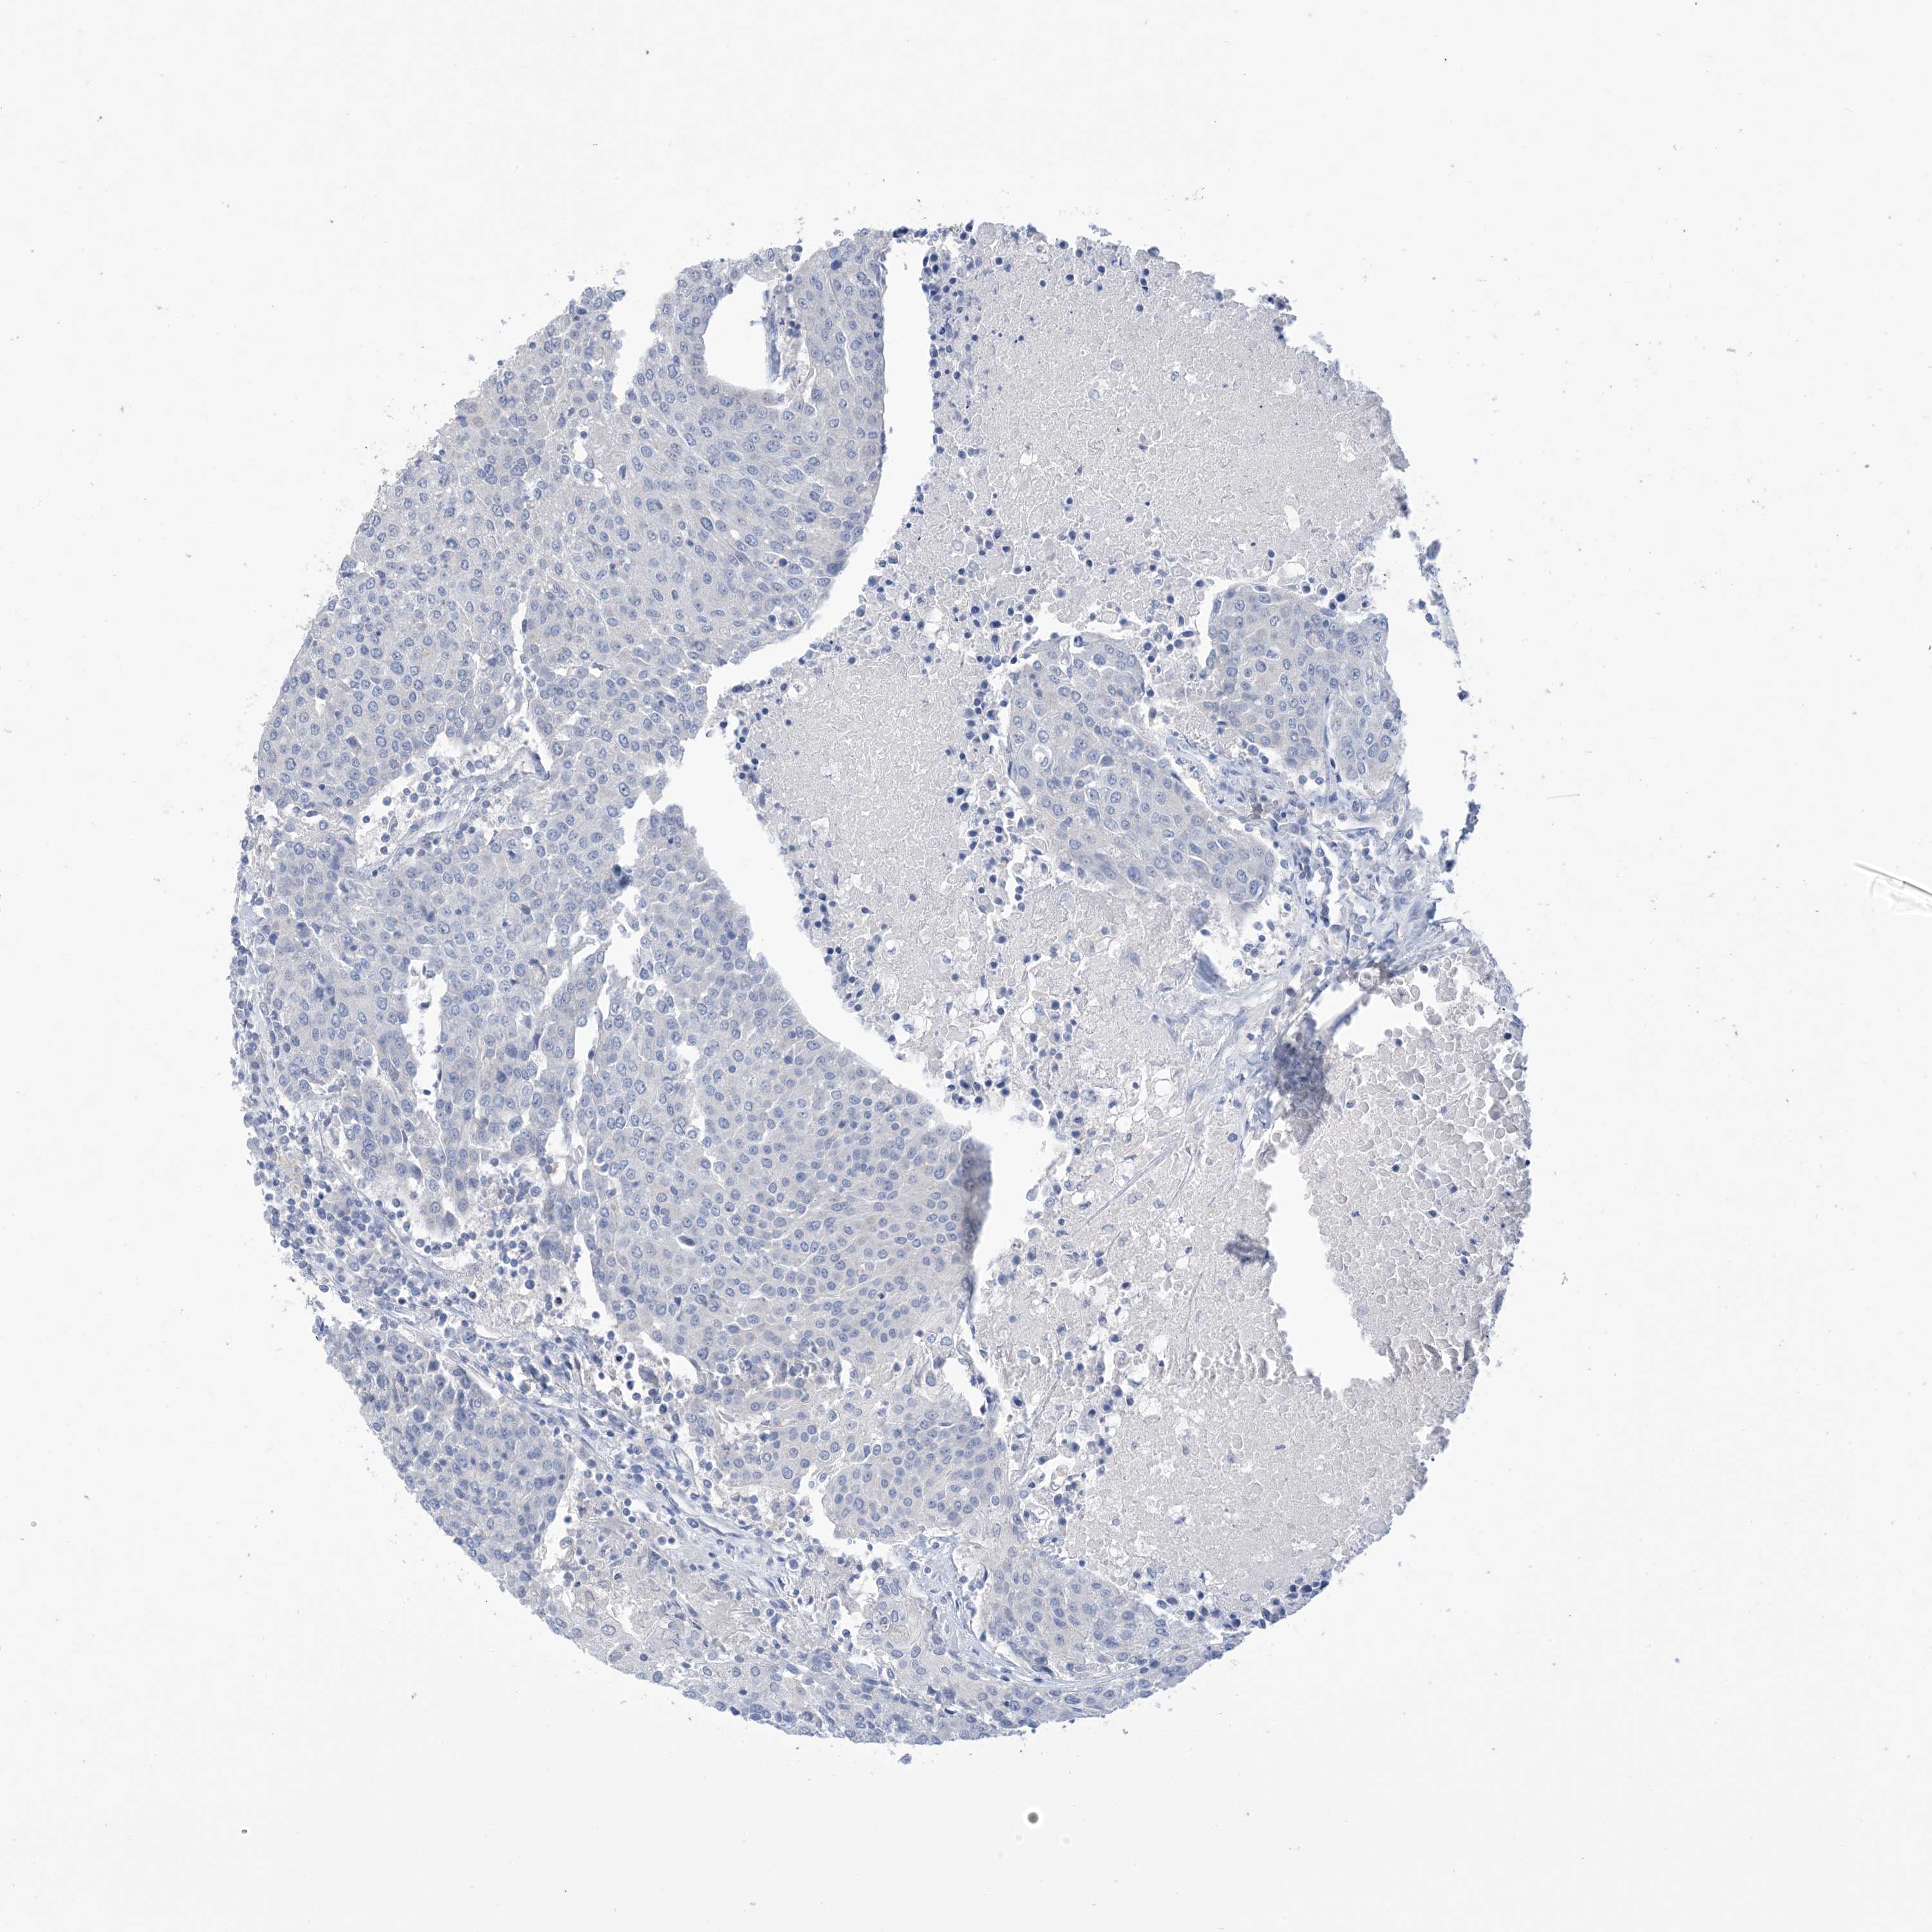

UROTHELIAL CANCER - Protein expressioni

A mouse-over function shows sample information and annotation data. Click on an image to view it in a full screen mode. Samples can be filtered based on level of antibody staining by selecting one or several of the following categories: high, medium, low and not detected. The assay and annotation is described here.

Note that samples used for immunohistochemistry by the Human Protein Atlas do not correspond to samples in the TCGA dataset.

Antibody stainingi

Antibody staining in the annotated cell types in the current human tissue is reported as not detected, low, medium, or high, based on conventional immunohistochemistry profiling in selected tissues. This score is based on the combination of the staining intensity and fraction of stained cells.

Each image is clickable and will lead to virtual microscopy that enables deeper exploration of all samples and also displays staining intensity scores, fraction scores and subcellular localization as well as patient and tissue information for each sample.

Antibody HPA049265

Antibody CAB037328

Urothelial carcinoma, High grade

Urothelial carcinoma, Low grade

Urothelial carcinoma, NOS